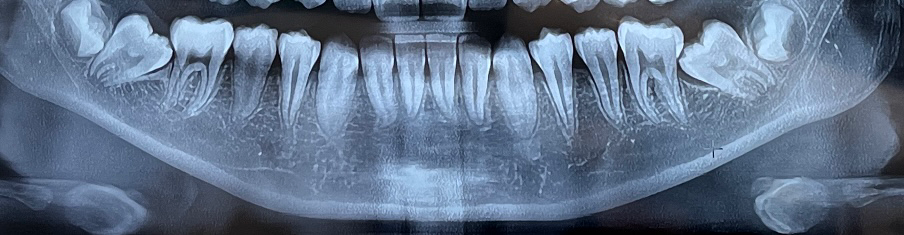

아래둘째어금니가 누워서 났어요. 다니던 치과에선 맨 마지막 사랑니들을 빼고 둘째어금니를 세우는 교정을 해야한다 하시네요.

둘째어금니가 똑바로 올라올 확률은 없을지 엑스레이사진좀 봐주세요..(왠만하면 사랑니발치도 교정도 안하고 싶거든요.. 아이가 너무 무서워해요..)

현재 사진으로서는 아래의 마지막 7번 치아가 누워 있으며 6번 치아에 걸려 있습니다. 이를 끌어올리기 위해서는 공간이 필요하며 뒤에 있는 치아를 제거해주셔야 합니다. 지금으로서는 교정적으로 커버하기 위해서는 뒤에 치아를 발치할 방법 밖에 없습니다.

가장뒤 어금니가 앞니에 걸려서 맹출이 되지 않고 잇는거 같습니다. 저런경우에는 어금니를 교정으로 맹출시켜야될것같습니다.

자연적으로 바르게 되기는 어렵고 사랑니를 발치하고 둘째 어금니는 교정을 통해 개선될수 있습니다.